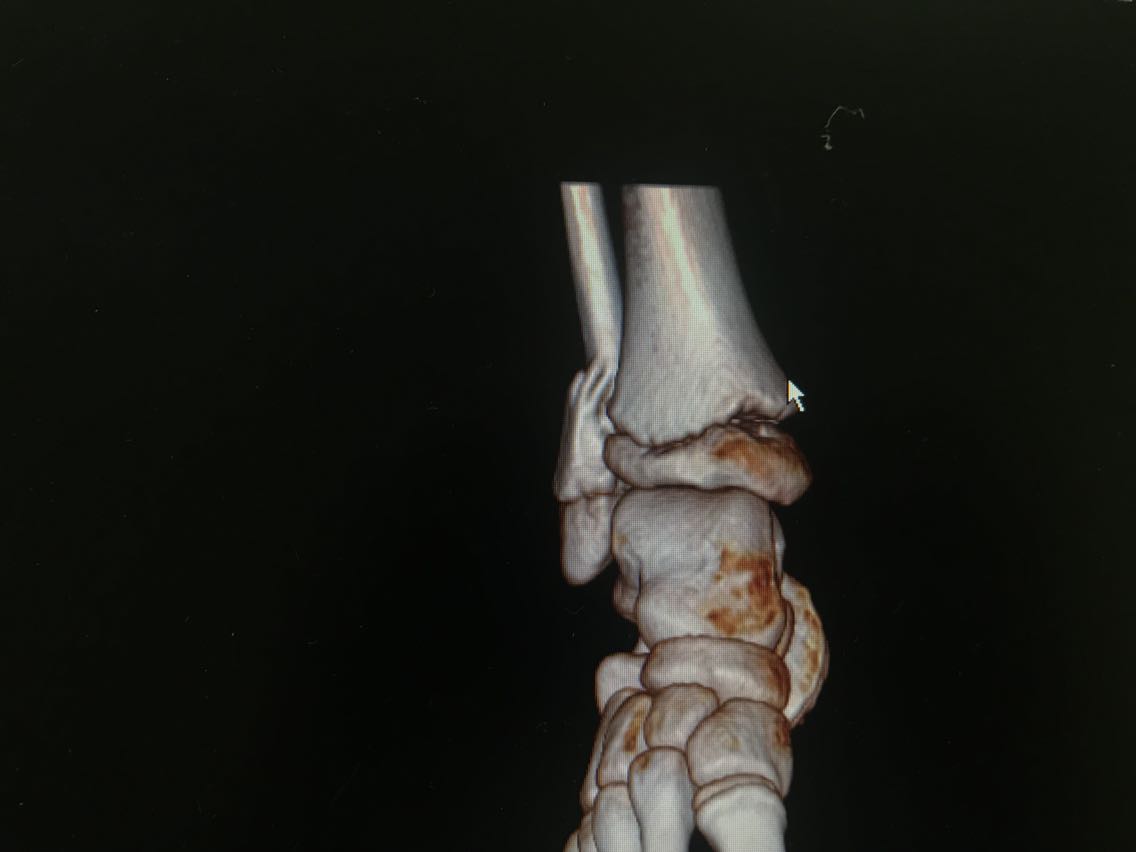

患者男性,10岁。 主诉:摔伤致右小腿疼痛,活动受限3+天 现病史:患者3+天前从高处摔下,高度约6米,摔下后右足着地。患者自述右侧小腿下段疼痛,可以耐受,意识清楚,呼之能应,无呕吐其他不适。右小腿肿胀、疼痛伴活动障碍,局部皮肤有明显青紫,无破损、流血等。遂至当地医院就诊,未予特殊处理,建议上级医院就诊。遂就诊于我院急诊科,行X线检查示:右侧腓骨下段骨折,断端稍成角、迂曲,右外踝关节间隙稍增宽,周围软组织肿胀。CT检查示:右侧腓骨下段骨折,断端稍成角、迂曲,右外踝关节间隙稍增宽,右胫骨干骺端与骺板间隙稍增宽,周围软组织肿胀。经我科医师会诊,以“右腓骨下段骨折”收入我科。患者自受伤以来精神睡眠可,食欲可,大小便正常,体重未见明显变化。 既往史无特殊。

查体:右小腿远端、足部肿胀明显,局部皮肤可见青紫,未见破损,右小腿远端皮温低,压痛不明显,桡动脉、足背动脉搏动可,右踝节活动受限,右足趾感觉、血运、活动正常,其余肢体未见明显异常。 辅助检查: X线检查,示:右侧腓骨下段骨折,断端稍成角、迂曲,右外踝关节间隙稍增宽,周围软组织肿胀。请结合临床及其它检查。右侧胫骨未见确切错位骨折征象。 CT检查,示:右侧腓骨下段骨折,断端稍成角、迂曲,右外踝关节间隙稍增宽,右胫骨干骺端与骺板间隙稍增宽,周围软组织肿胀。请结合临床及其它检查。